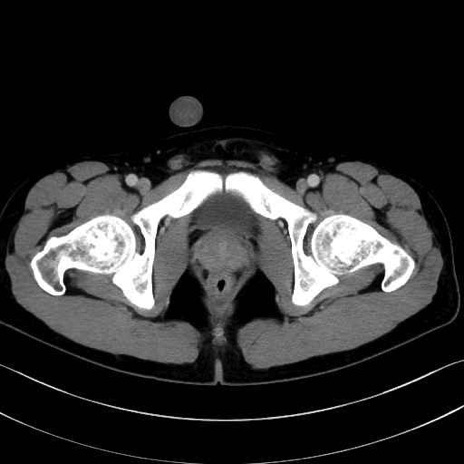

大腿方形筋(Quadratus femoris muscle)のCT画像の解剖

大腿方形筋 (Quadratus femoris)